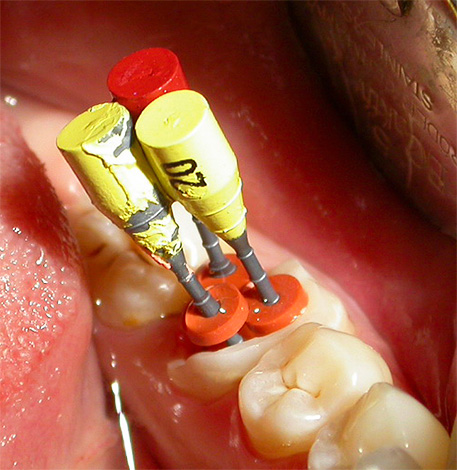

Le immagini seguenti mostrano esempi di preparazione di cavità: